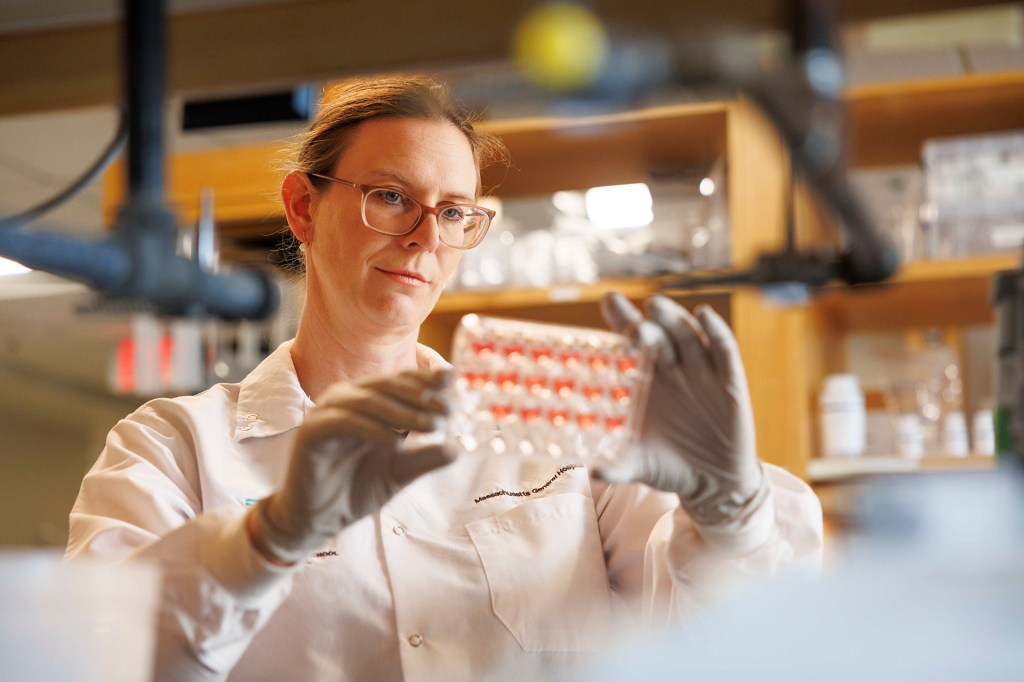

What might cancer treatment teach us about dealing with retinal disease?

Joan Miller’s innovative thinking led to therapies for macular degeneration that have helped millions, made her better leader